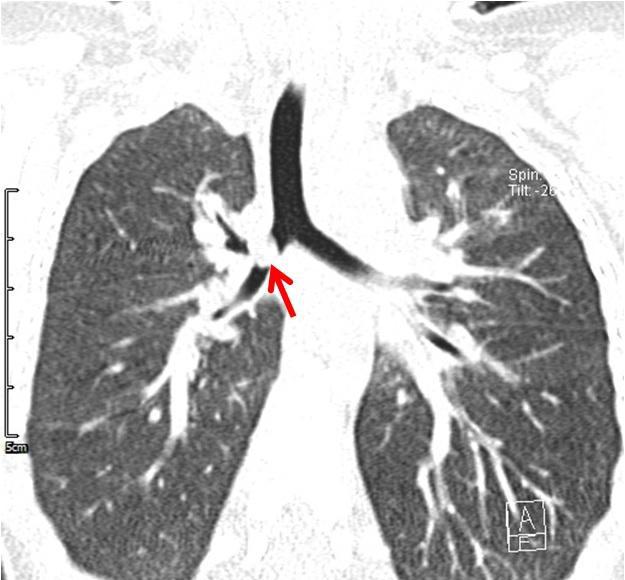

灰尘嘛,气管吸入,肯定堆在气管两侧啦. 下图:尘肺.(4)